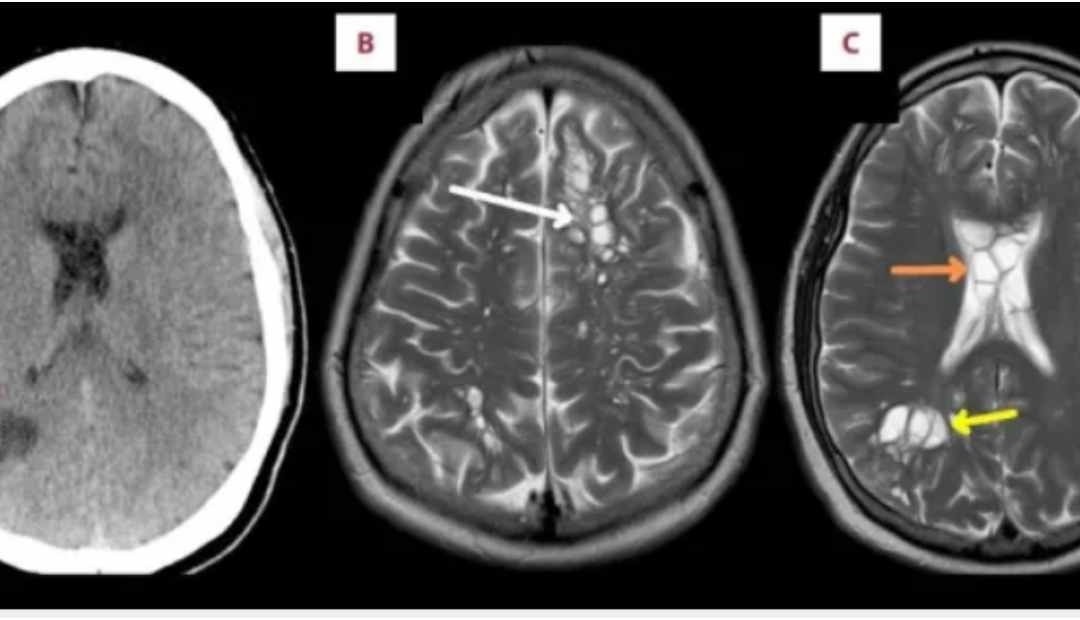

Un paciente de 52 años en la Florida, Estados Unidos, fue al médico por migrañas crónicas que cada vez eran más frecuentes y los medicamentos que usaba ya no funcionaban. Al hacerle exámenes las imágenes fueron sorprendentes: tenía múltiples quistes en ambos lados de su cerebro que resultaron ser huevos de gusano; la causa de la hinchazón de su cráneo.